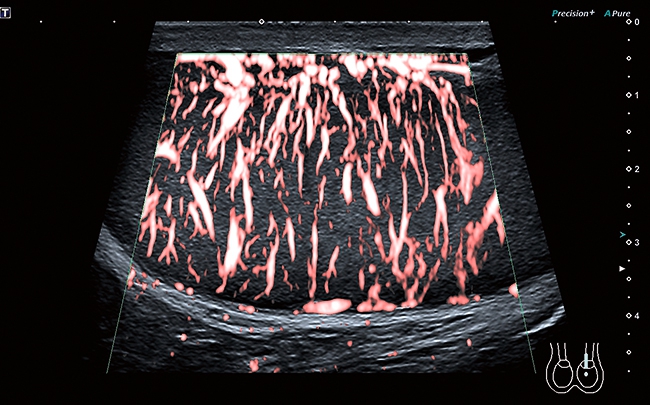

• Технология SMI для визуализации микроциркуляторного русла и отображения низкоскоростного кровотока в микрососудах

Функция получения трехмерного изображения в режиме цветового допплеровского картирования

Эта функция поможет вам получить качественные трехмерные цветные изображения при проведении исследования. Нужного эффекта удается достичь за счет использования датчиков 3D/4D в В-режиме с последующим восстановлением объемной структуры в режиме ЦДК. Кроме того, данная функция совместима с режимом Freehand 3D.